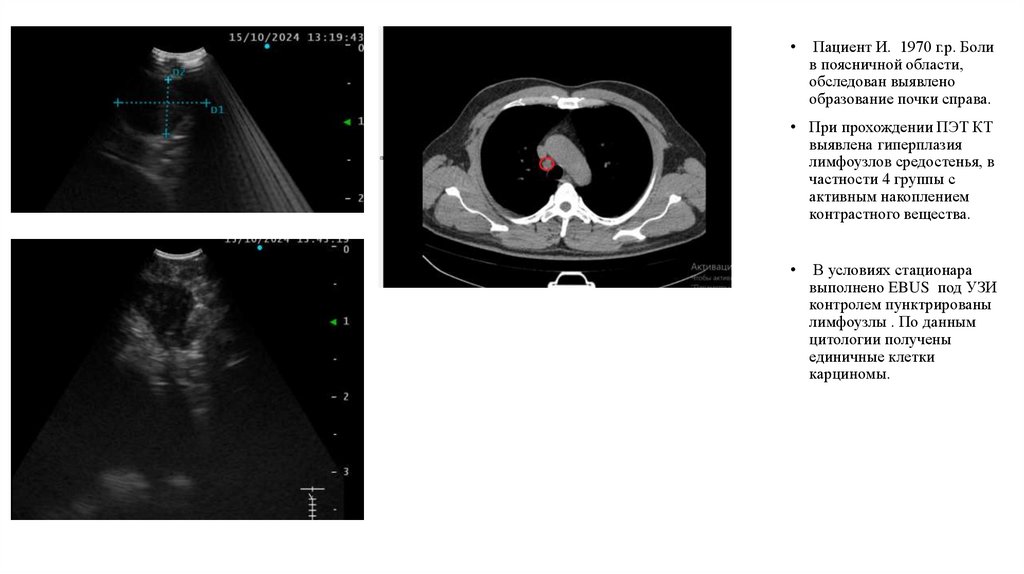

Пациент И. 1970 г.р. Боли

в поясничной области,

обследован выявлено

образование почки справа.

• При прохождении ПЭТ КТ

выявлена гиперплазия

лимфоузлов средостенья, в

частности 4 группы с

активным накоплением

контрастного вещества.

В условиях стационара

выполнено EBUS под УЗИ

контролем пунктрированы

лимфоузлы . По данным

цитологии получены

единичные клетки

карциномы.